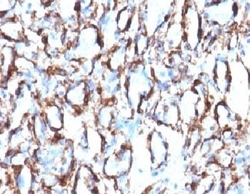

- Main image

- Experimental details

- Formalin-fixed, paraffin-embedded human colon carcinoma stained with alpha Smooth Muscle Actin antibody (ACTA2/791). This image was taken for the unmodified form of this product. Other forms have not been tested.